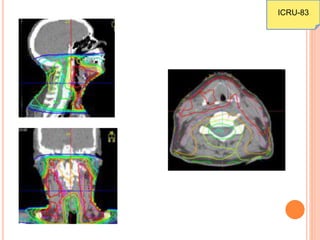

 In IMRT, the delineation of the target and normal

structures has to be very precise due to the high

conformality achieved by IMRT as compared to 3-

DCRT. This benefit is especially seen in concave

volumes.

 The tolerance for the MLC leaf position is smaller

when using the MLC for IMRT than for 3-DCRT.

ICRU-83

 There are 3 levels of reporting as discussed in the

previous report (ICRU-50)

 Level 3 – includes biological factors which are still

under evaluation and not in routine clinical use

(TCP, NTCP, EUD)

 Dose-volume based calculations (Level 2 reporting)

are routinely used now rather than ICRU reference

point reporting

 Using DVH, we can find the presence (but not the

location) of minima and maxima in the contoured

 The location of these minima & maxima can be

seen in sections-wise viewing the isodose

curves/colour wash.